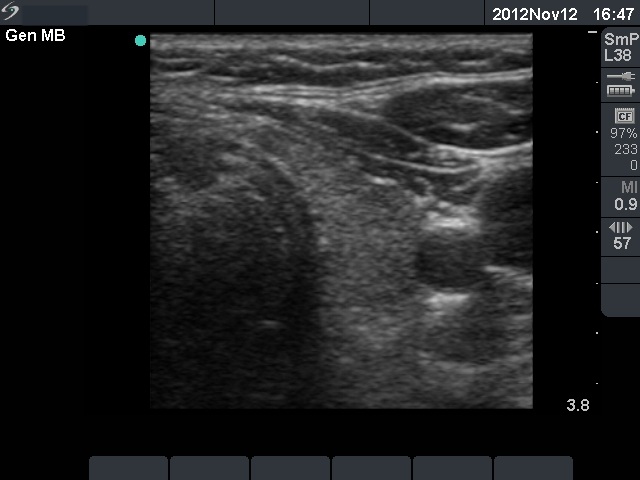

Follow-up examination 4 weeks later (3rd row of images):

He had no complaints with euthyroid hormone levels (TSH 2.41 mIU/L, FT4 14.1 pM/L) and normal CRP (1.1 mg/L) and ESR 9 mm/H.

Ultrasonography demonstrated an almost complete normalization.